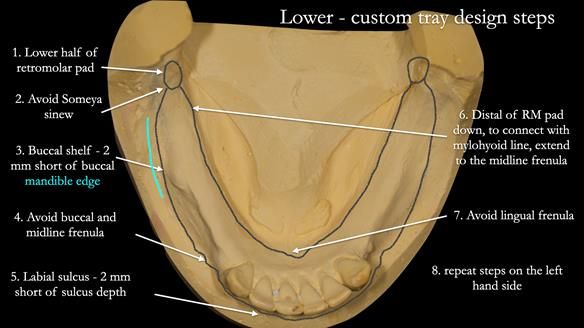

This newsletter describes the full protocol workflow of a complete upper denture and a lower partial denture for Jo.

The clinical situation and treatment process is shown in detail below. I provided the clinical work. Rowan Garstang provided the technical work. This treatment took 25 visits over a period of 12 months.